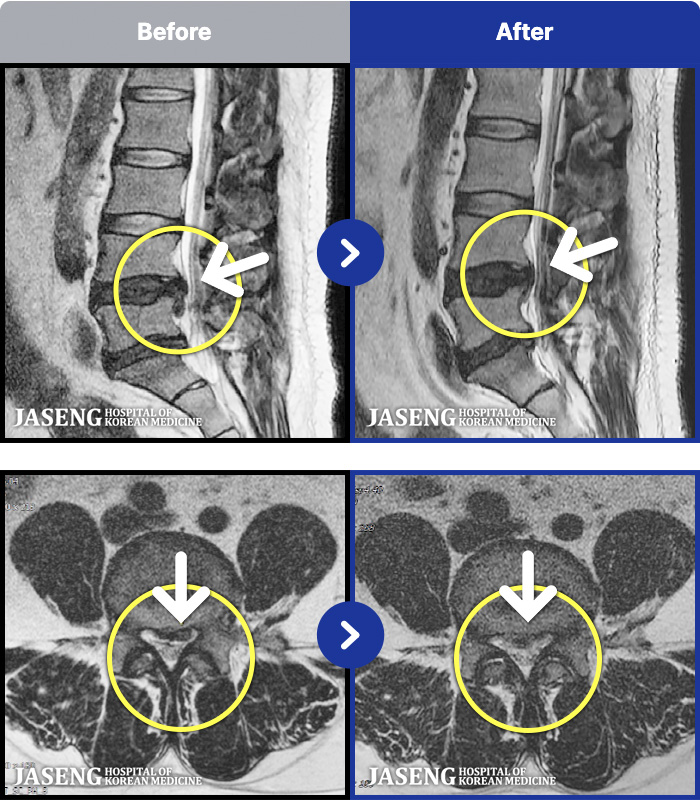

[뱸] 19.11.28~25.05.06

ȯںп Ǹ ǿ ԿǾ, ο ġ ۿ Ƿ ġḦ Ͻñ ٶϴ.